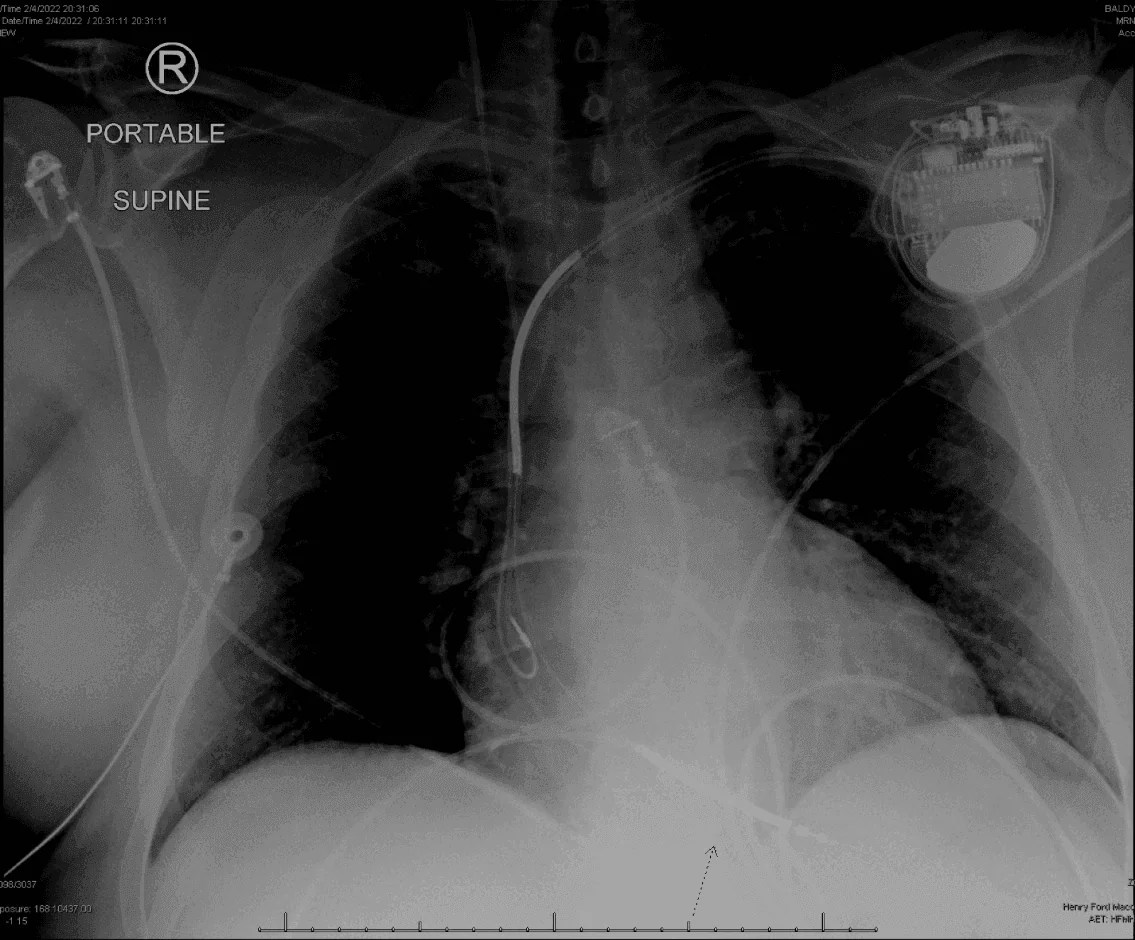

From www.researchgate.net

Chest Xray of a male patient after SICD implantation. The generator... Download Scientific Pain In Left Arm After Icd Implant This is not uncommon for icd recipients, especially in the first months or year. Some of the risks that may be encountered during the implant procedure include the following: Shoulder pain and disability ipsilateral to the implant site is a common complication of cardiac rhythm device implantation, yet very little has been published about this. Formation of a blood clot;. Pain In Left Arm After Icd Implant.